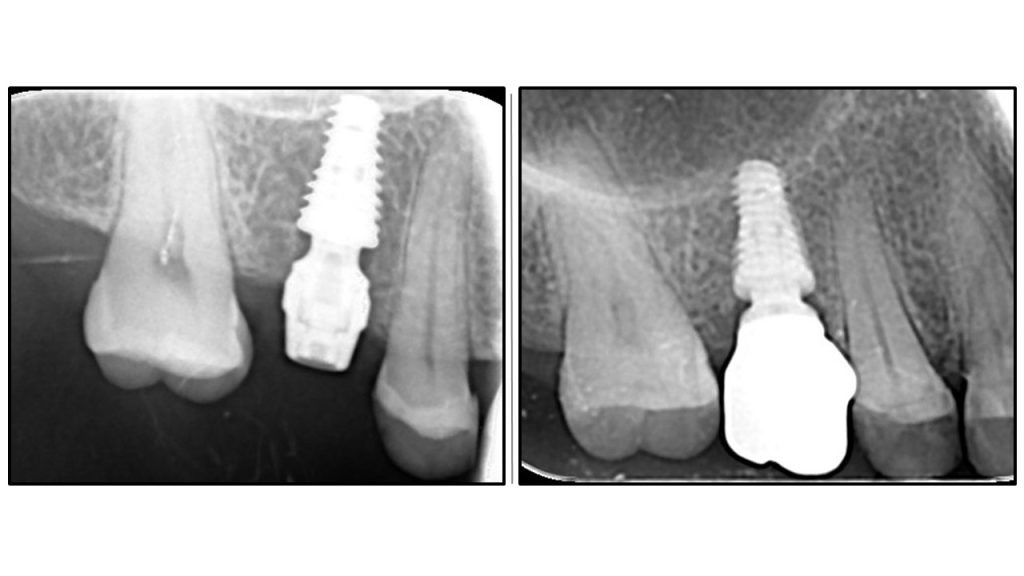

Радиографска анализа: стабилност костине крошне